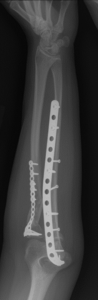

Dr. Riehl treats orthopaedic conditions both operatively and nonoperatively and performs a wide array of orthopaedic procedures including, but not limited to, the following:

Nonunion and malunion repair related to post-traumatic conditions and/or prior surgery

Acute fracture care of the pelvis and the extremities